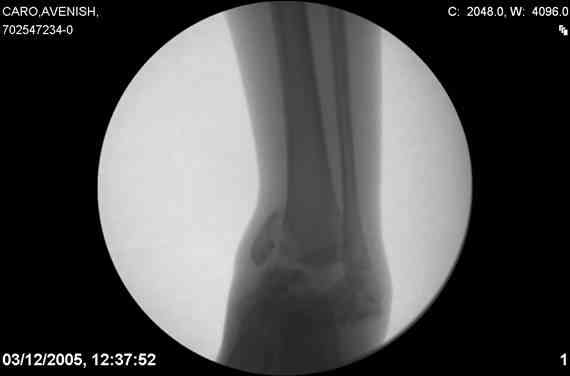

ya by popytalsya sobrat talus anatomichno,seichas pozdno operirovat iz za oteka,po etomy distrakziya apparatom budet optmalna.Posyalu vam podobyai moi sluchai.

14 years old girl

Fall from height ( 3rd floor)